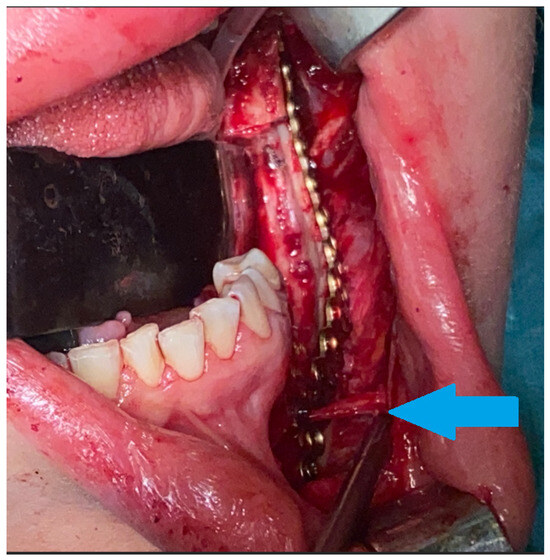

Figure 3. Intraoperative view after reconstruction and superior mandibular body marginectomy. A thin layer of intact lower mandibular border was kept and used for stable bone osteosynthesis (titanium 2.0 plates, Medartis, Basel, Switzerland) to prevent any secondary pathological fracture. The mental nerve was spared and safely retracted away (blue arrow). Surgical ostectomy was made with burrs and Lindemann drills. We avoided any unnecessary segmental resection, skin scarring, and the necessity for a bigger procedure, meaning that this surgical procedure was performed with a good overall success rate. CGCG cannot be diagnosed in any laboratory testing, and histopathology sometimes might be insufficient, where it can be misdiagnosed as BT, while radiological appearance might mimic other odontogenic cysts or tumors. On the other hand, fully grown and active BT is easily diagnosed with blood examination for calcium–phosphate markers alone. Perhaps very early in the BT formation stage, its prolonged slow growth or atypical manifestation and close relation between BT and CGCG can lead to such diagnostic dilemmas. It is worth noticing that small local lesions can be treated with nonsurgical means or local minimally invasive surgical approaches [1,2]. Some studies advice local tumor injections of calcitonin, interferon alpha, or intratumor steroids; however, the success rates vary in the known literature [3,4,5]. On the other hand, the scope of more aggressive and advanced lesions might require different surgical approaches, and in the literature, its possible outcomes vary from bone curettage and ostectomy to radical segmental osteotomies with immediate bone reconstructions or surgical debulking. Based on the following, the scope of surgery is case-driven and depends greatly on the tumor size, shape, location, and the adjacent bone condition. The presented case outlines how such a big lesion was treated by the authors with a great overall surgical success. Because of some radiological similarities between BT and CGCG, careful patient examination is mandatory, and additional bone markers should always be evaluated, and even repeated over time. It is quite important to identify any PHP or a simple CGCG lesion in good early timing to improve the patient’s general condition. Without an improved excisional biopsy in order to examine the entire specimen, its highly possible that the patient could suffer for a long time because of general status worsening caused by the effects of PHP calcium–phosphate on multiple organ systems over various intensities and time frames, causing, for example, bone osteoporosis, kidney stones, nephrocalcinosis, hypertension, cardiovascular disturbances, neuropsychiatric symptoms, pancreatitis, and muscle and joint weakness, among others [3,4,5].